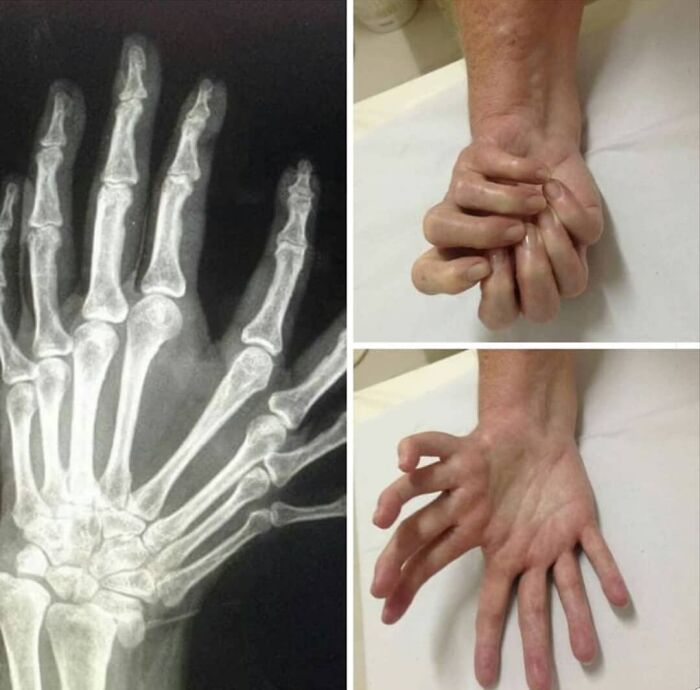

La dimelia cubital o síndrome de la mano en espejo es una anomalía congénita rara de la extremidad superior caracterizada por ausencia de radio, duplicación del cúbito y polidactilia simétrica.